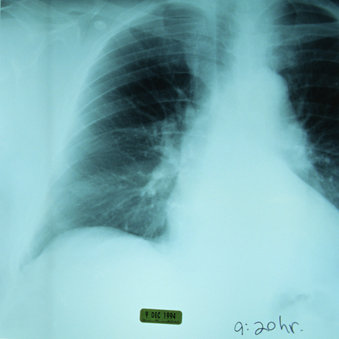

При туберкулезе врач может назначить пациенту применение Амикацина . Это очень действенное лекарственное средство, использовать которое разрешается только в строгом соответствии с инструкцией .

Следует отметить, что Амикацин относится к резервным препаратам для лечения туберкулеза . Как правило, его назначают в комбинации с другими препаратами резерва .

Противотуберкулезные препараты "второго ряда" - канамицин, амикацин, капреомицин; этионамид (протионамид); офлоксацин, ципрофлоксацин; циклосерин (теризидон); ПАСК - назначают в случаях, когда по каким-либо причинам невозможно использовать основные средства .